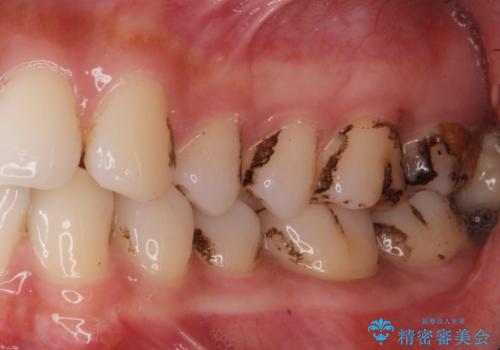

着色が気になる(エアフロー)

- 着色が気になるとの事で来院。

エアフローでしっかり着色を取り除きました。

着色が目立たなくなり大変満足して頂けました。